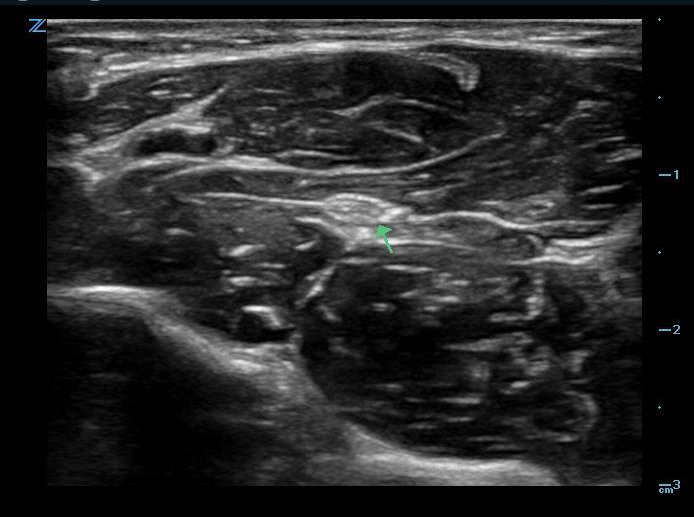

Figure 1. Median nerve in the mid-forearm

- Place the probe transversely on the volar surface of the forearm.

- The median nerve is located in the central volar compartment on a fascial plane below the flexor digitorum superficialis.

- If the nerve is not apparent, try fanning or tilting the probe to compensate for anisotropy.